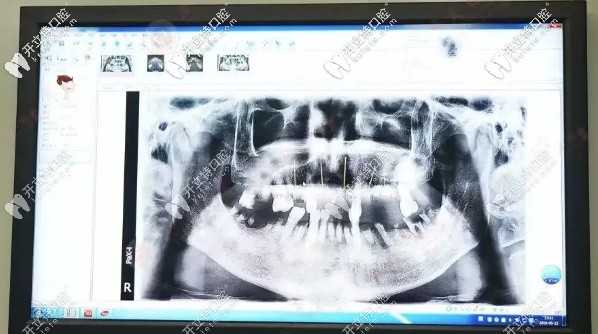

爺爺歲數(shù)大了,牙齒隨著年齡增長(zhǎng)也在松動(dòng)脫落再加上之前也沒(méi)有重視過(guò)刷牙的問(wèn)題,也從來(lái)沒(méi)注意口腔健康。造成現(xiàn)在能用的牙齒幾乎沒(méi)有,連吃飯都成了問(wèn)題,更別說(shuō)吃肉了,長(zhǎng)此以往,營(yíng)養(yǎng)跟不上,心情也不好了,那段時(shí)間見(jiàn)到爺爺都瘦了好多,這樣下去情況很糟。牙齒拍的片子